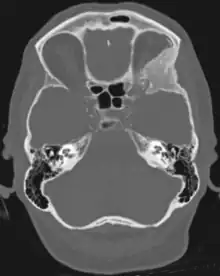

Sphenoid wing meningioma in computed tomography which shows the reactive orbital hyperostosis

Tumors found in the external third of the sphenoid are of two types: en-plaque and globoid meningiomas. En plaque meningiomas characteristically lead to slowly increasing proptosis with the eye angled downward. Much of this is due to reactive orbital hyperostosis. With invasion of the tumor into the orbit, diplopia is common. Patients with globoid meningiomas often present only with signs of increased intracranial pressure. This leads to various other symptoms including headache and a swollen optic disc. The differential diagnosis for sphenoid wing meningioma includes other types of tumors such as optic nerve sheath meningioma, cranial osteosarcoma, metastases, and also sarcoidosis. Following the physical exam, the diagnosis is confirmed with neuro-imaging. Either a head CT or MRI with contrast such as gadolinium is useful, as meningiomas often show homogenous enhancement. Angiography looking for signs like stretched arteries may be used to supplement evaluation of vascular involvement and to determine whether embolization would be helpful if surgery is being considered.